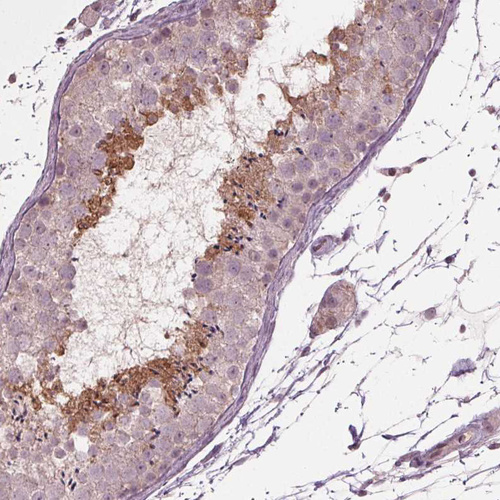

Immunohistochemical staining of human lymph node shows moderate positivity in non-germinal center cells.